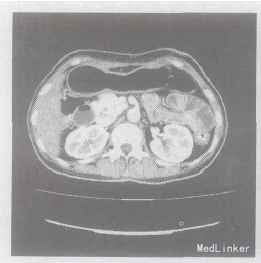

查体: 上腹轻压痛, 其他无异常。 辅查:胃镜检查示: 反流性食管炎。腹部B超及CT示: ① 胆囊切除术后改变; ② 胰体尾部结构未见显示; ③ 胃及十二指肠扩张改变。妇科B超、肠镜、脑电图, 血管彩超检查均未见明显异常。

入院后完善相关检查行ERCP,示 : 斜向上走行的短胰管,长31.63mm,体尾部未见任何胰管显示。小肠泛影葡胺造影: ① 胃动力减低; ② 小肠未见梗阻现象。实验室检查:C肽释放试验+血清胰岛素测定: 空腹胰岛素2.0mU/L; 餐后1h 5.50 mU/L ; 餐后2h 2.90 mU/L; 餐后3h 3.60 mU/L ; 空腹C肽0.8ng/ml; 餐后1h 1.70ng/ml; 餐后2h 1.30 ng/ml; 餐后3h 0.99ng/ml。糖耐量检测: 空腹血糖15.93mol/L ; 餐后1h 23.12mol/L ; 餐后2h 19.50mol/L ;餐后3h 20.10 mol/L 。考虑诊断: 先天性短胰腺。